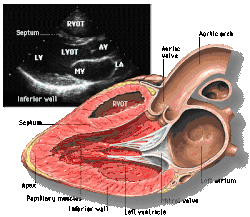

![]() Parasternal long axis |

Each figure contains a TTE with a black background, and a corresponding colored illustration. | Patrick J. Lynch and C. Carl Jaffe, Yale University, 2006. | ||||||||||

Click on a figure to enlarge it and see some parts of the heart identified. RV, right ventricle; LV, left ventricle; RA, right atrium; LA, left atrium; TV, tricuspid valve; MV, mitral valve; AV, aortic valve; RVOT, right ventricular outflow tract; LVOT, left ventricular outflow tract |